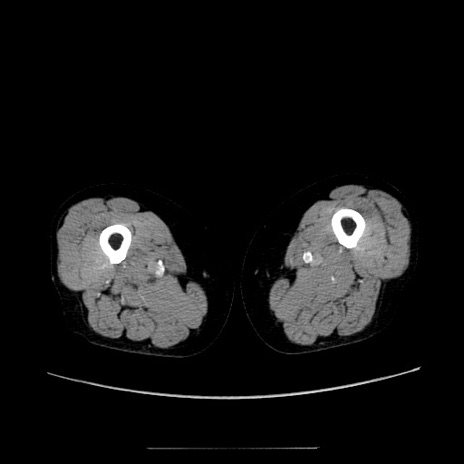

【症例】70歳代女性

【主訴】お腹が張る

【現病歴】1週間くらい前から腹部膨満の自覚あり。昨日夜から増悪したため、本日救急外来受診。

【身体所見】意識清明、BT 36.5℃、BP 165/106mmHg、HR 80bpm、SpO2 98%、腹部:膨満、軟、自発痛・圧痛なし、触診にて不快感あり、腸蠕動音:減弱

【データ】WBC 12600、CRP 1.04